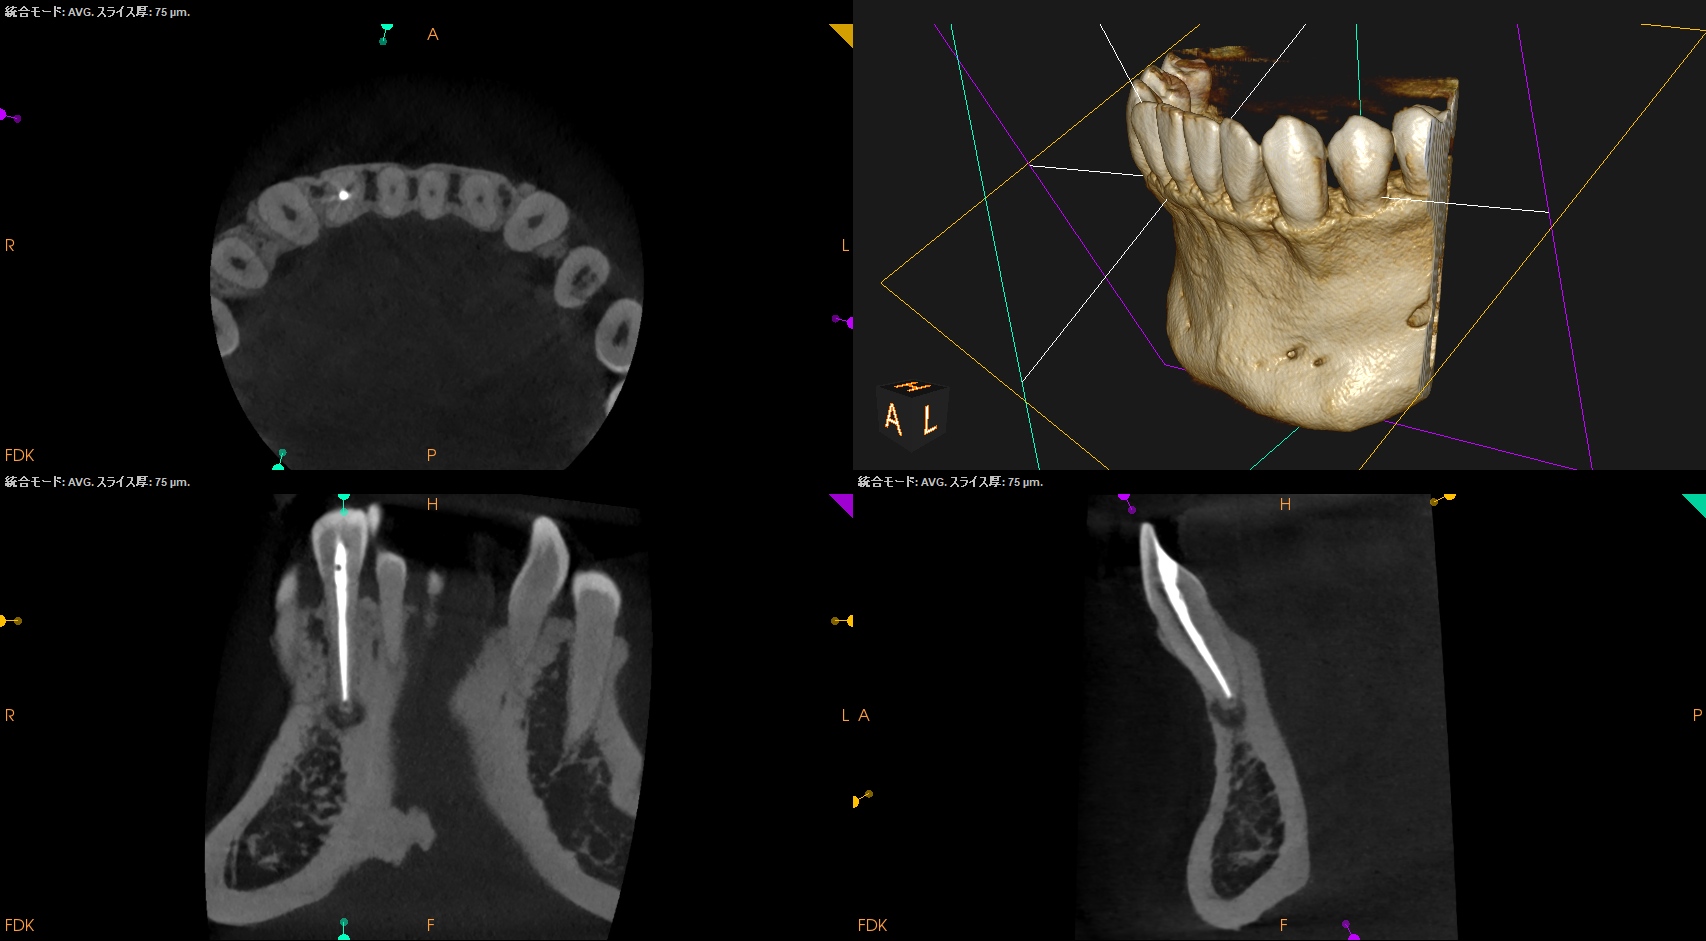

CBCT(2025.4.16)

Pre-op Endo Diagnosis(2025.4.16)

Pulp Dx: Normal Pulp Tissues

Periapical Dx: Symptomatic apical periodontitis

Recommended Tx: RCT

#26 RCT 9M recall(2026.1.7)

初診時と比較した。

問題が縮小していることがわかる。

が、消失ではないのでまた半年後に見せてもらうことになった。